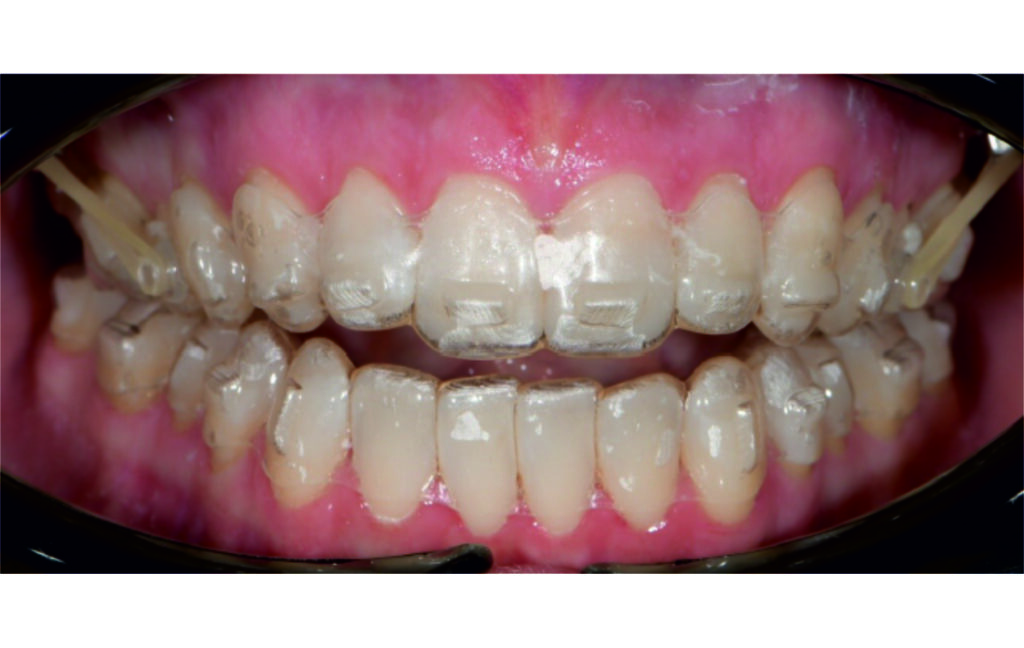

Treatment progress

A 1.5 mm deviation of the upper dental midline to the patient’s left was noted, along with a slight mandibular midline shift to the right, likely due to asymmetrical mandibular growth observed in the facial structure. Severe mesial rotations of teeth 16 and 26 were evident in the initial records. As derotation of 16, 26, 17, and 27 progressed up to aligner 16, the premolars in segments I and II moved distally, resulting in a bilateral Class I relationship, as intended in the initial treatment plan.

Derotation of 16 26 allowed Class II correction.

Vertical vector of elastic traction on buttons and IZC helped with the open bite correction.